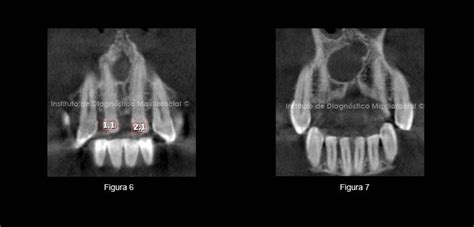

Actualmente existe mucha controversia con respecto a la longitud de la obturación, muchos estudios han establecido que idealmente debe estar localizada en la constricción cemento-dentinaria determinada por muchos autores a 0.5mm del ápice radiográfico (3, 4, 10, 13, 19, 23). Cuando los conductos radiculares se obturan sin llegar al foramen apical, las reacciones por lo general desaparecen al cabo de tres meses y por último se da una reparación completa, en cambio los dientes con conductos radiculares sobreobturados han mostrado reacciones inflamatorias crónicas persistentes, además de una mayor tendencia a la proliferación epitelial y a la formación quistes.

En conclusión, para muchos investigadores, la constricción apical es considerada como el punto final apical ideal para la instrumentación y obturación en el tratamiento endodóntico, debido a que más allá de la constricción, el conducto se amplía y desarrolla un mayor flujo vascular. Cuando existe alguna alteración durante el proceso de obturación, la respuesta del tejido periapical es alterada. Este tipo de fenómenos puede provocar una estimulación de los restos epiteliales de Malassez induciendo la formación de quistes periapicales. Tanto la reparación como la respuesta periapical ante el proceso de obturación, está influenciada por la presencia de un proceso infeccioso previo. Existen interacciones específicas ya establecidas y la inclusión de un nuevo irritante puede retrasar el proceso de reparación, ocasionar la agudización del fenómeno y/ perpetuar su respuesta. La presencia de bacterias en la porción externa del cemento radicular y la imposibilidad de su remoción afectan el pronóstico de reparación y podría asociarse a fenómenos de exacerbación (19).